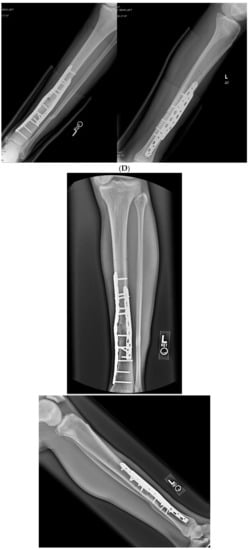

3.3. Case 3-Single-Plane Correction with Nail: Tibia

An adult male with no comorbidities presented with varus malunion following intramedullary tibial nailing, reporting symptomatic medial knee pain (Figure 8A). The CORA analysis revealed a varus deformity of 12 degrees. With a deformity in the coronal plane, surgical access was through an anterior approach using a focal dome osteotomy for correction. The anterior compartment was elevated, and a drill bit was placed in the CORA, with a parallel drill guide used to draw the arc with a second drill bit. The osteotomy was completed with an osteotome. The alignment was maintained during reaming using a temporary plate (Figure 8B). The patient underwent compression nailing using a magnetic motorized nail, allowing for subsequent compression as needed after discharge (Figure 8C). The patient felt pain-free at 12 weeks, yet was encouraged to return for regular follow-up examinations and X-rays until radiographic healing. Patient lost to follow-up after 6 months (Figure 8D).

Figure 8.

(A) Adult male with varus malunion deformity after a prior tibia fracture and nailing. (B,C) Patient underwent focal dome osteotomy with compression nailing using a magnetic motorized nail for early and subsequent nail compression. (D) Patient declined to follow-up after 12 weeks, citing absence of pain. Patient returned at 6 months at request of surgeon, still without pain. Magnetic nail recompressed. Patient lost to follow-up after 6 months.